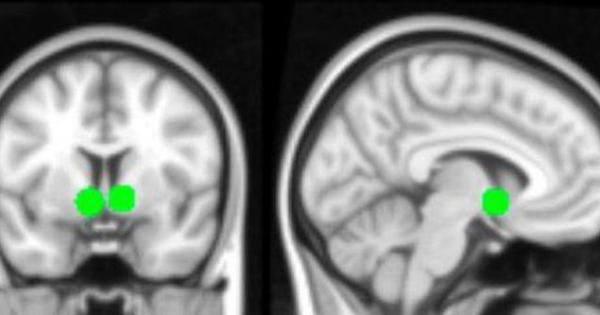

Lo studio è dei ricercatori dell'Imperial College di Londra e dell'Università di Cambridge. La loro ricerca ha portato gli studiosi a riscontrare una importante riduzione del livello di intelligenza in chi ha contratto il virus e poi è guarito dal Covid. Lo studio è stato pubblicato su The Lancet.

Inoltre i risultati hanno confermato i dati precedenti sui sintomi del Covid di lungo periodo, la cosiddetta "nebbia del cervello", i problemi di concentrazione e la selezione delle parole.

Più è stata grave la forma in cui si è contratta la malattia, più aumentano i problemi. Così, nei pazienti che hanno avuto bisogno di essere collegati al ventilatore polmonare, si sono manifestate le maggiori difficoltà: il loro QI è sceso di sette punti. Questo non è stato osservato nemmeno tra coloro che hanno avuto un ictus.

I ricercatori hanno inoltre verificato se esiste una correlazione tra il declino delle capacità cognitive e il tempo trascorso con l'infezione del virus. Alla fine non hanno trovato nessun legame, il Covid-19 ha causato conseguenze irreversibili.